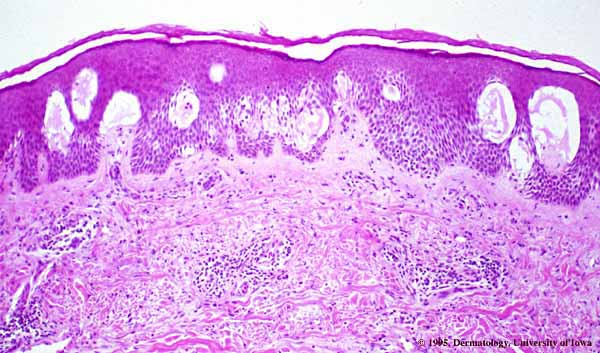

Acute contact dermatitis = التهاب ا لجلدالحاد بالتماس